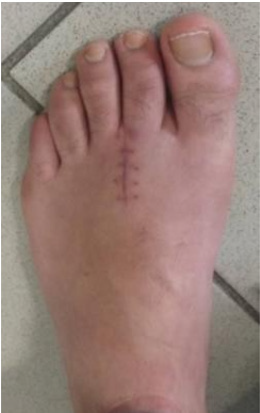

The postoperative period was uneventful, and the patient was discharged the day after surgery. Partial weight bearing was allowed with a Barouk type shoe for the first 4 weeks and gradually progressing to full weight bearing. Active and passive mobilization of the joint was encouraged immediately. The patient presented a good clinical and imagiological evolution, with serial follow-up radiographs showing good screw position with complete bone healing after 8 weeks (Figures 6 & 7). At final follow-up examination, 12 months after surgery, the patient presented no pain and full range of active and passive motion of the second metatarsophalangeal joint. Radiographs showed complete union of the fracture with no evidence of avascular necrosis or arthritic changes of the second metatarsal head (Figure 8). He had resumed sports and daily life activities with no limitations.

Figure 6: (a) Anteroposterior and

(b) Oblique postoperative radiographs at 4 weeks

showing good bone healing evolution.

Figure 8: (a) Anteroposterior and

(b) Oblique postoperative radiographs at 12 months

follow-up showing complete union of the fracture with no

evidence of avascular necrosis or arthritic changes of the

second metatarsal head.